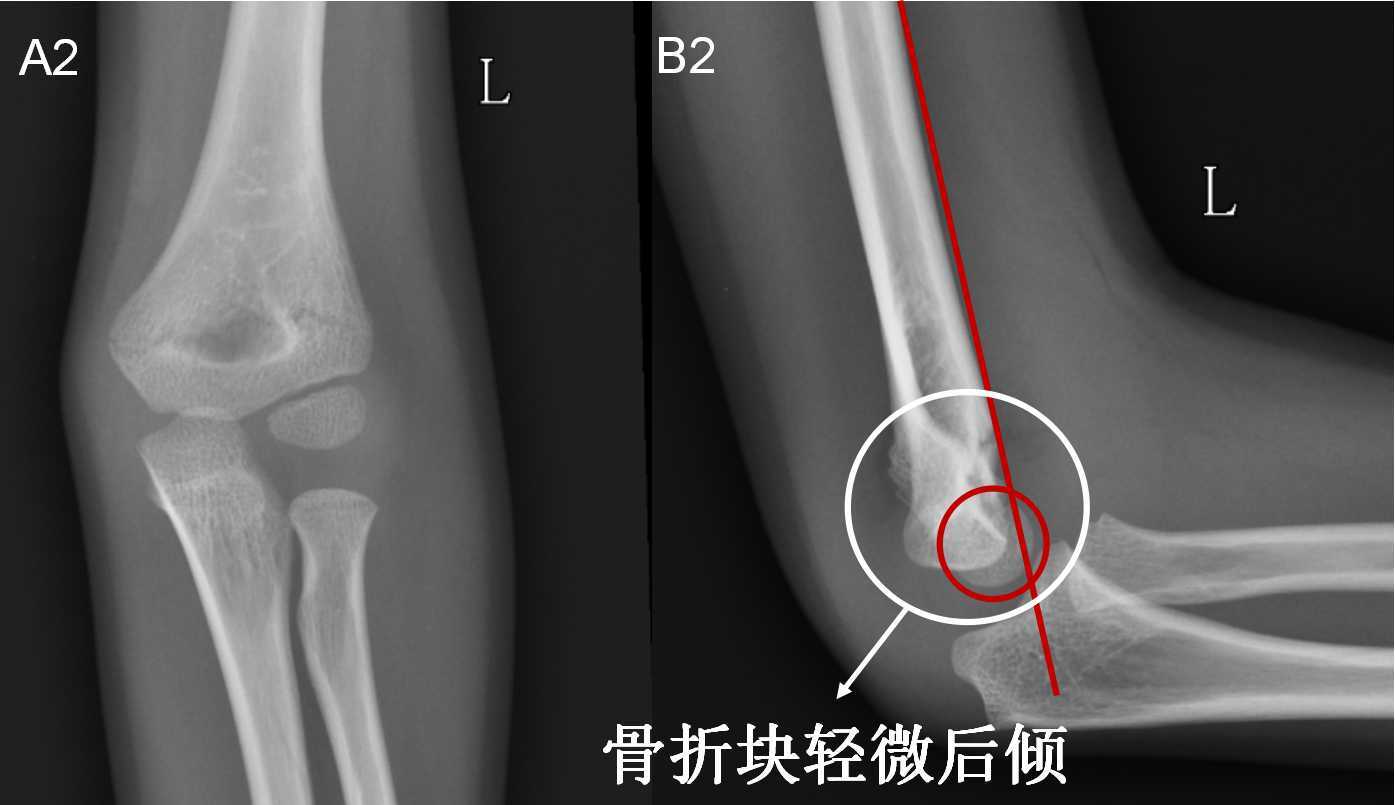

7种 肘部损伤x片详细图解 小头

一分钟让您明白肱骨髁上骨折什么时候要手术 什么时候不用手术 肱骨骨折 肱骨骨折

病例分享 常见儿童肘部骨折及治疗

儿童肘部损伤x线诊断涂占海 Ppt Download